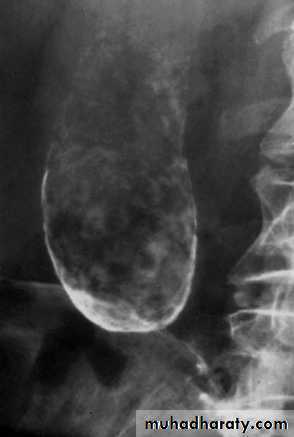

Plain radiogaph:

Radiopaque gall stones in 10%Porcelain GB.. calcified GB..25% CA.

Limey bile

Gas in the wall, emphysematous cholecystitis

Porcelain GB

Radiopaque Gall stones